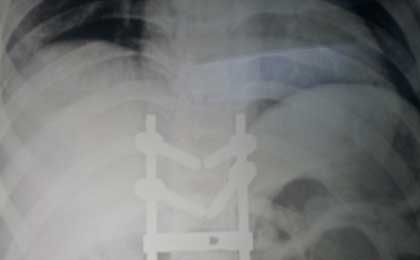

DORSAL SPINE INTRA OPIMAGE

DORSAL SPINE FIXATION INTRA OP